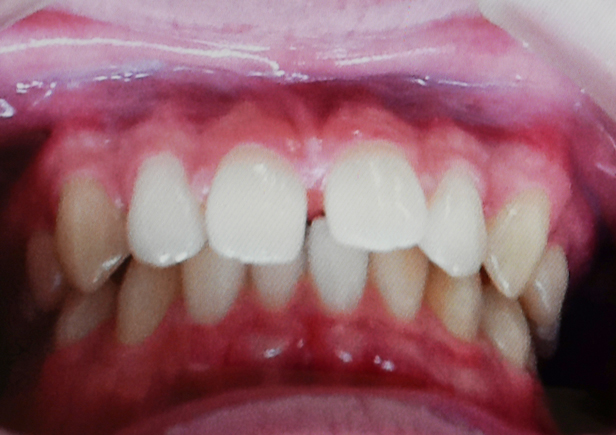

矯正bofore

矯正after

矯正種類 マウスピース矯正

症例 すきっ歯

治療期間 令和5年9月〜令和6年3月 6ヶ月

性別/年代 男性/20歳9ヶ月

治療費 上下顎 : 280,000円(税別)

短期間でしっかり空隙も無くなりました。

上顎だけの治療でしたが、その過程で下顎の叢生(でこぼこ)も綺麗になった好症例です。